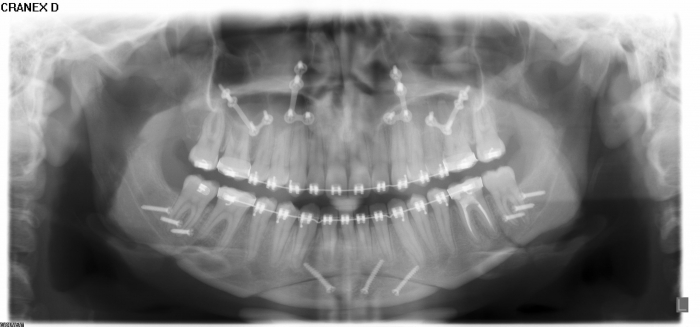

Rx Panoramico inicial - Clínica Cliniface

Rx Panoramico inicial